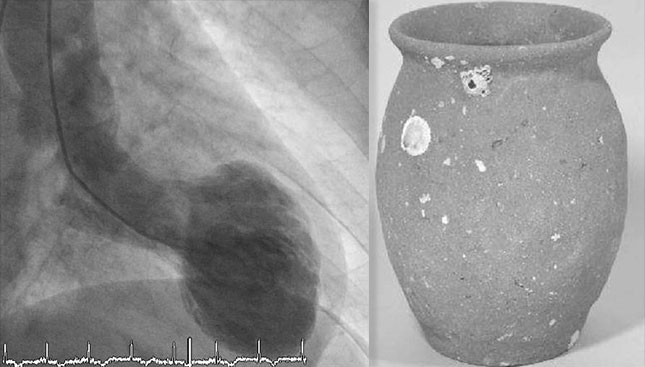

TCM因发作时LV心尖呈气球样(左)与传统日本章鱼鱼篓的圆形底部和窄口相似而命名(称为“Takotsubo”[章鱼壶])(右)。该病多见于女性,部分原因是由于压力引起的儿茶酚胺释放对心肌产生影响(心肌顿抑和微梗死)。其它机制包括多支心外膜冠状动脉痉挛,冠状动脉微血管功能障碍和受损心肌脂肪酸代谢异常。心肌不同阶段对高水平儿茶酚胺的反应性存在差异(例如,心尖部对负性肌力的肾上腺素更敏感)似乎支持儿茶酚胺的作用。